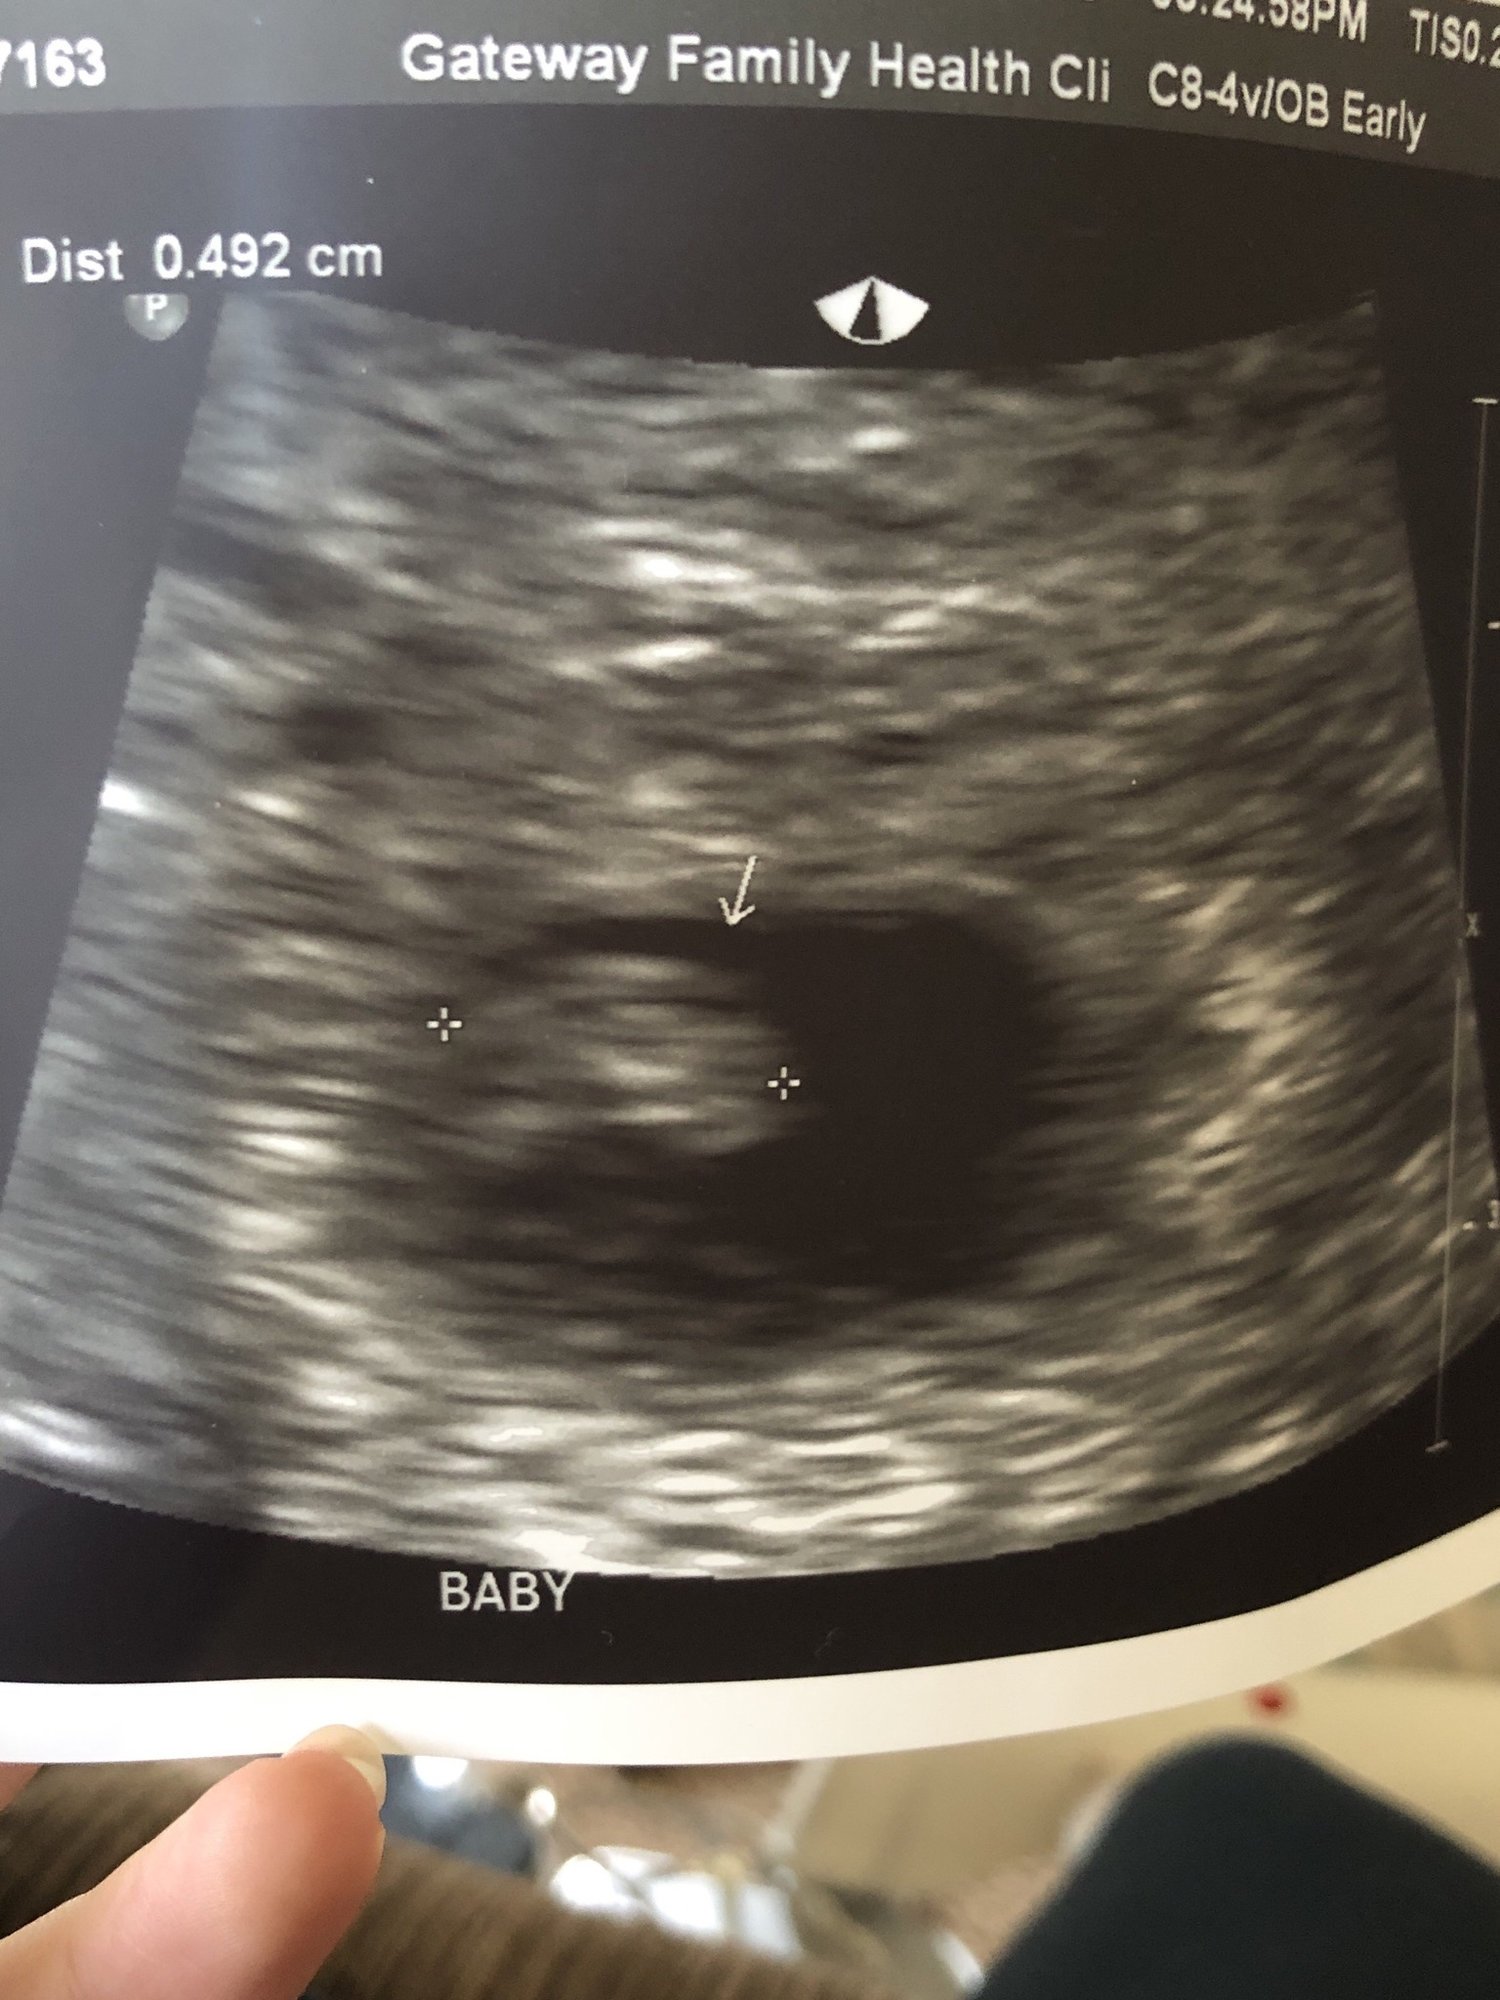

Not too much to see but there's a little baby there with a heartbeat of 122 BPM

The two black dots to the right are the hematoma bleeds😥 Pic was taken far away like this because they are more focused on the SCH.

Since I am very high risk i will be getting weekly ultrasounds to watch the bleed. Praying next week the baby will have grown and the hematoma will be smaller. Keeping faith.